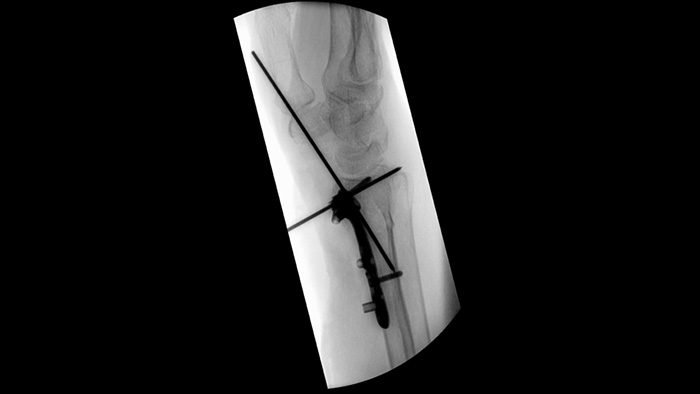

O MetalSmart exclui automaticamente os artefatos de metal causados por implantes metálicos para fornecer maior qualidade de imagem e um controle eficiente da dose durante procedimentos ortopédicos e em pacientes com implantes metálicos, se comparado a sistemas sem exclusão de metal. O BodySmart promove diagnósticos por imagem certos da primeira vez e eficiência de dose ao adaptar automaticamente o campo de medição à área de interesse.

Obturadores assimétricos únicos aumentam a flexibilidade de colimação e o ajudam a colimar a anatomia usando a colocação independente do obturador com a ponta do dedo. Você pode ajustar os obturadores e a orientação de imagem enquanto estiver na última retenção de imagem sem usar radiação.